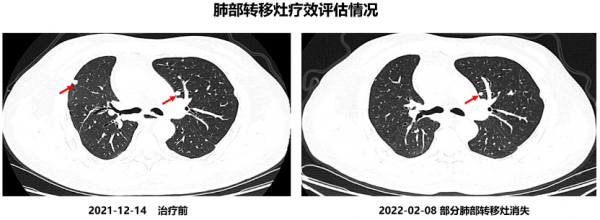

患者2021年12月21日開始口服吡咯替尼(400mg qd,早餐後30分鐘內口服),口服吡咯替尼1月半後,於2022年2月8日行靶向治療後第一次療效評估。複查結果提示右頸部淋巴結縮小62%。原先肺部多發轉移病灶,吡咯替尼治療後,大部分肺部轉移病灶消失。